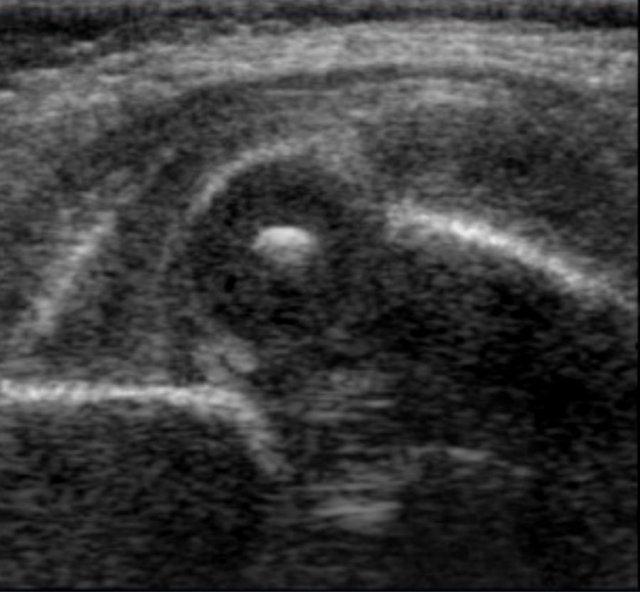

Đây là khớp háng loại IIc.

Mái ổ cối xương bị thiếu hụt nghiêm trọng với bờ xương tròn đến gần như phẳng.

Góc alpha là 46 độ.

Chỏm xương đùi vẫn được bao phủ bởi mái sụn và viền sụn.